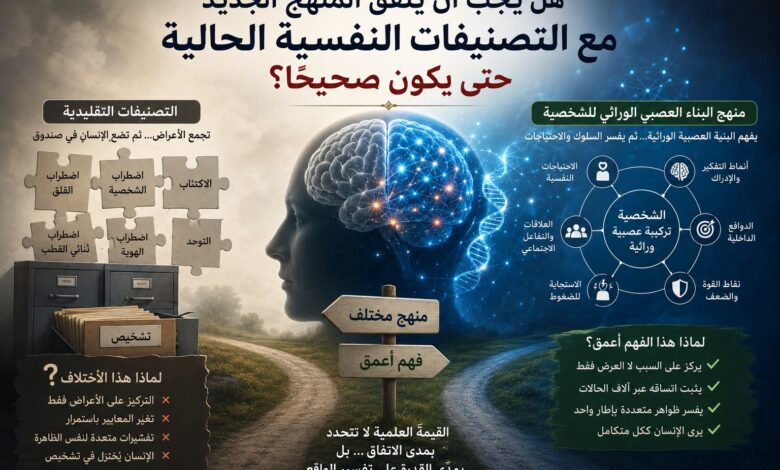

كل أسبوع تقريبًا تنشر دوريات علم الأعصاب والطب النفسي عشرات الدراسات التي تكشف اختلافات جديدة في الدماغ. مرة نجد اختلافًا في شبكات الاتصال العصبي، ومرة في طريقة معالجة المعلومات، ومرة…

أكمل القراءة »لم يعد علم الأعصاب الحديث يسير في الاتجاه القديم نفسه الذي كان يختزل الإنسان في متوسطات عامة، أو يفسر السلوك من خلال أعراض ظاهرة، أو يتعامل مع الدماغ كأنه نسخة…